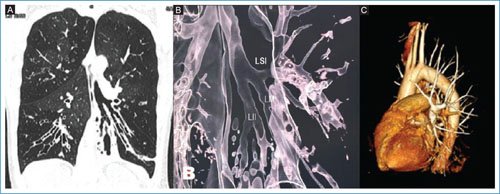

Mujer de 44 años con antecedente de bronquiectasias y múltiples neumonías de repetición. En el seguimiento presenta sobreinfección de bronquiectasias por Pseudomonas aeruginosa resistente. Se realiza imagen de tomografía (Fig. 1A) con alteración a nivel de la ramificación bronquial que sugiere sospecha de lóbulo pulmonar accesorio. Sin embargo, en la imagen de reconstrucción bronquial se evidencia presencia de tres lóbulos pulmonares izquierdos (Fig. 1B) con bronquio inferior acompañado de arteria lobar (Fig. 1C). Las pruebas de función pulmonar reportaron volumen espiratorio forzado en un segundo (FEV1) 0.9, capacidad vital forzada (FVC) 2.14, FEV1/FVC 42, capacidad de difusión del monóxido de carbono 18.1 ml/min/mmHg.

Figura 1. A: tomografía de tórax con ventana pulmonar y corte coronal a nivel de bronquio principal izquierdo. Se observan bronquiectasias arrosariadas (estrella) y división de tres bronquios: superior, medio e inferior. B: reconstrucción en tercera dimensión que demuestra carina secundaria con división de tres bronquios lobares. C: reconstrucción vascular del patrón arterial observando irrigación para lóbulo superior, medio e inferior de lado izquierdo.